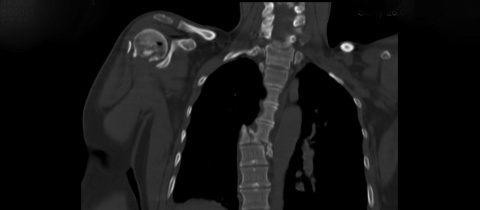

Intuitivně jsem tušila, že opravdu něco není v pořádku. Výsledky CT byly alarmující, ne jedna bezvýznamná zlomenina obratle, nýbrž zlomenin devět, z toho šestý hrudní obratel rozdrcen, další zlomeniny těl obratlů a trnových výběžku. Páteř v oblasti šestého obratlu zcela vychýlena a navíc tvořící pěkný zlom. K tomu pět zlomených žeber.

A jak jste zvládla onen „výstup na Sněžku“, cca 2 měsíce po převozu do ČR, pokud správně počítám? Článek je varováním před jednáním pojišťovnou, ale nevešlo se do něj, jak se páteři podařilo „konzervativně srůst“ ? Snímek páteře vypadá děsivě…

podle toho rtg páteře jsi měla z pekla štěstí, že ještě chodíš…

Při čtení mi běhal mráz po zádech a ten snímek páteře je fakt hodně děsivej!!!

Jana

Zdravím,pokud jste přežila to,co je na snímku páteře,tak už přežijete všechno.Vaše mícha je z nějakého materiálu vyvinutého pro kosmonauty? Ostatní zdravotní problémy zvládnete,o tom vůbec nepochybuji a fandím.